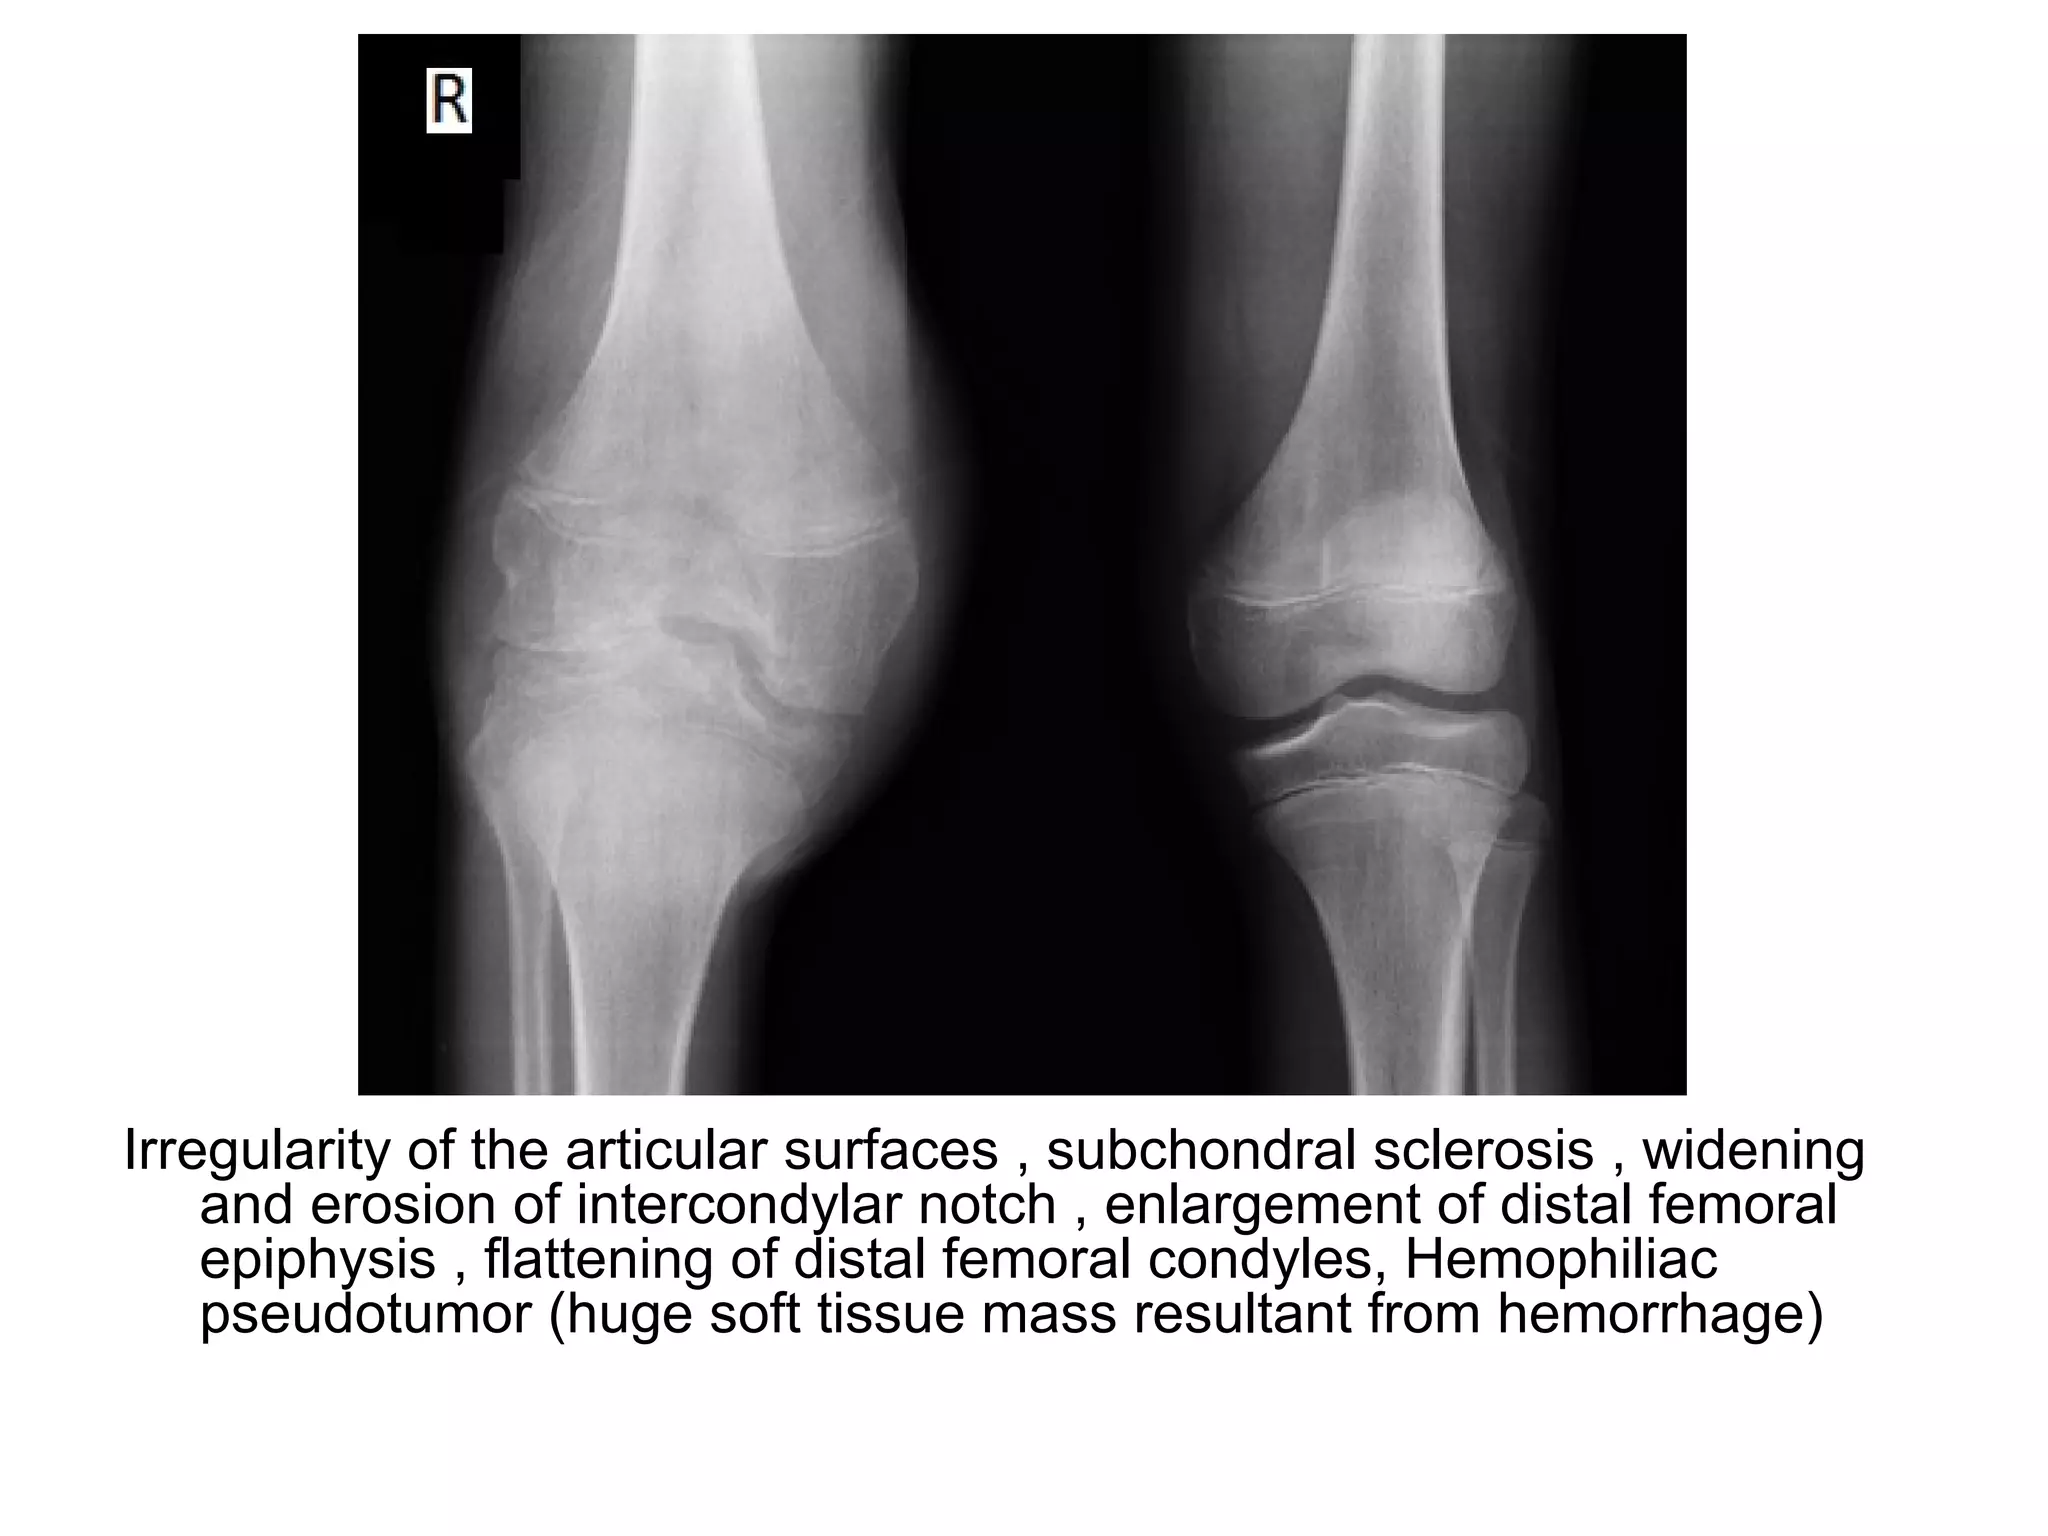

Irregularity of the articular surfaces , subchondral sclerosis , widening

and erosion of intercondylar notch , enlargement of distal femoral

epiphysis , flattening of distal femoral condyles, Hemophiliac

pseudotumor (huge soft tissue mass resultant from hemorrhage)

Irregularity of the articular surfaces and subchondral sclerosis ,

hemophiliac pseudotumor (hemorrhage had such an extent that a

huge soft tissue mass resulted)